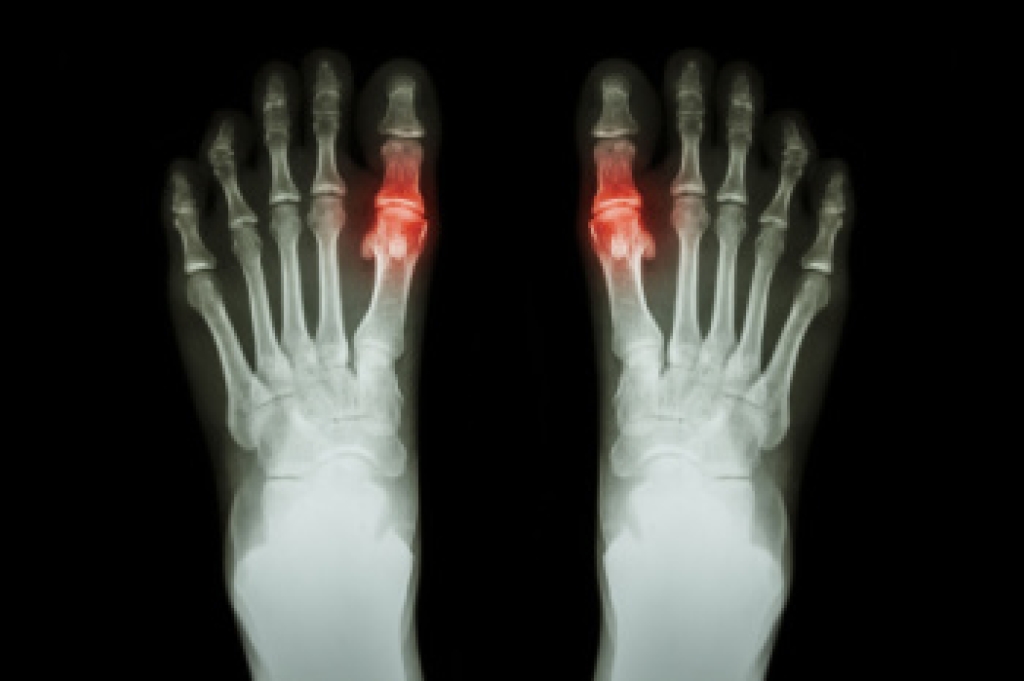

Plantar fasciitis is a painful condition that causes heel and arch discomfort, especially with the first steps in the morning. Exercise can play an important role in easing symptoms and improving function over time. Strengthening the small and large muscles of the foot helps support the arch and reduce strain on the plantar fascia. Working the muscles of the hips, especially those that stabilize movement, can also improve alignment and reduce stress placed on the feet while walking or running. Simple stretching on its own can help loosen tight tissues and improve flexibility, which may decrease tension and pain. These approaches are often more effective when combined and guided properly. A podiatrist can create a plan that targets your specific needs and monitor your progress to prevent setbacks. If you have ongoing heel pain, it is suggested that you seek care from a podiatrist.

Stretching the muscles in the foot is an important part in any physical activity. Feet that are tight can lead to less flexibility and make you more prone to injury. One of the most common forms of foot pain, plantar fasciitis, can be stretched out to help ease the pain. Stretching can not only ease pain from plantar fasciitis but also prevent it as well. However, it is important to see a podiatrist first if stretching is right for you. Podiatrists can also recommend other ways to stretch your feet. Once you know whether stretching is right for you, here are some excellent stretches you can do.